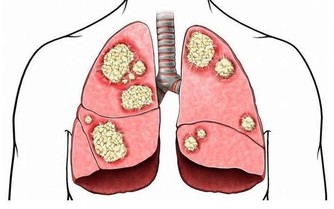

防止動脈粥樣硬化、調養「三高」、提高記憶、預防和治療心腦血管疾病有著持久而有效的作用,

同時對於抑制人體癌細胞的生成及轉移有很大的作用。適合全家人一起食用,老少皆宜!